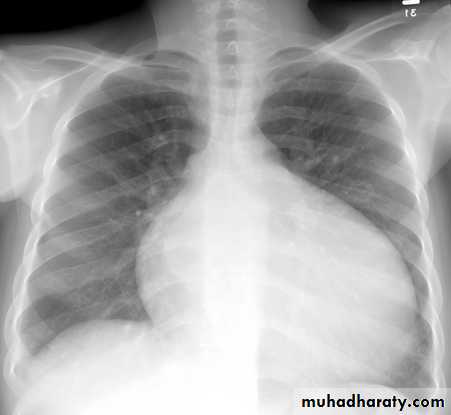

Chest X-Ray: cardiomegaly and pulmonary congestion

Echocardiogram: Chamber enlargement and global hypokinesisCXR